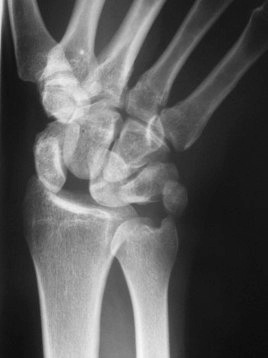

One of the most important and commonly injured ligament in the wrist is the scapholunate ligament.  This ligament stabilized the scaphoid bone to the lunate bone.  If this ligament is injured it can cause significan dysfunction to the wrist.  This injury needs to be recognized and treated appropriately.